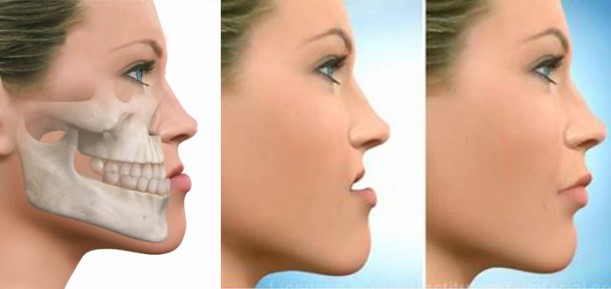

- Protrusiones dentoalveolares

- Discrepancia de las relaciones anteroposteriores

Discrepancia de las relaciones anteroposteriores.

En estos casos hay un aspecto estético negativo manifestado por el paciente siendo motivo de la consulta.

Uno de los principales objetivos de la terapia con extracciones es proporcionar un volumen dentario compatible con las dimensiones existentes del arco. Este procedimiento, cuando es bien diagnosticado y se realiza un tratamiento correcto, proporciona una mejor función masticatoria, de dicción, deglución y estética proporcionando tratamientos más estables.

La extracción de dientes no afecta la efectividad de la masticación ya que al término del tratamiento ortodóntico debe existir una correcta interrelación y armonía entre los dientes y sus maxilares, mejorando sustancialmente la eficacia de la masticación, así como una estética agradable.